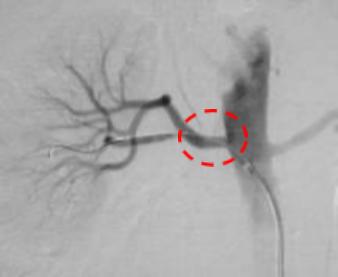

介入治疗后,狭窄消失,血流通过顺利,下肢疼痛症状消失。

治疗后